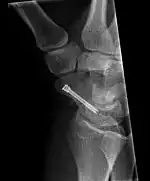

The scaphoid can be slow to heal because of the limited circulation to the bone. Fractures of the scaphoid must be recognized and treated quickly, as prompt treatment by immobilization or surgical fixation increases the likelihood of the bone healing in anatomic alignment, thus avoiding mal-union or non-union.[5] Delays may compromise healing. Failure of the fracture to heal ("non-union") will lead to post-traumatic osteoarthritis of the carpus.[1]: 189 One reason for this is because of the "tenuous" blood supply to the proximal segment.[2] Even rapidly immobilized fractures may require surgical treatment, including use of a headless compression screw such as the Herbert screw to bind the two halves together.

Scaphoid fractures may be difficult to diagnose via plain x-ray, its so repeat x-ray may be used at a later date, or cross-sectional imaging via MRI or CT scan.[5]